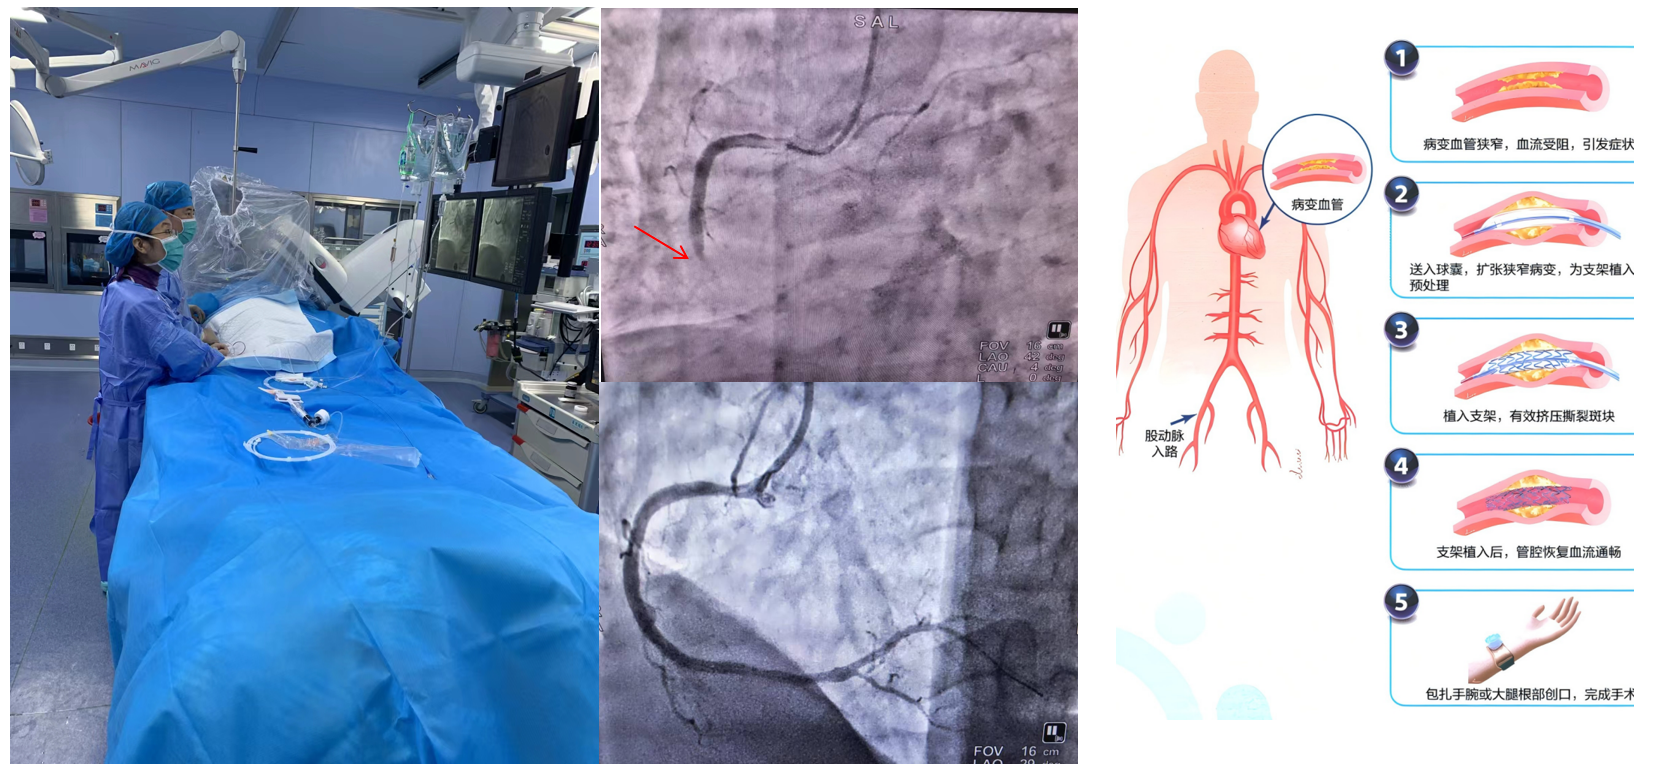

1.經(jīng)皮冠狀動(dòng)脈介入治療(PCI):是用心臟導(dǎo)管技術(shù)疏通狹窄甚至閉塞的冠狀動(dòng)脈管腔,從而改善心肌血流灌注的一組治療技術(shù)。在血管嚴(yán)重狹窄或閉塞病變段放置支架或藥物球囊,以保證血管長期暢通,是冠脈介入手術(shù)的主流。

適應(yīng)癥性穩(wěn)定型冠心病、不穩(wěn)定型心絞痛、非ST段抬高型急性心肌梗死、急性ST段抬高型心肌梗死、PCI術(shù)后再狹窄或并發(fā)癥。

f4d740e1d5b64bd7945f05bce7d78af0.Png

經(jīng)皮冠狀動(dòng)脈介入治療(PCI)